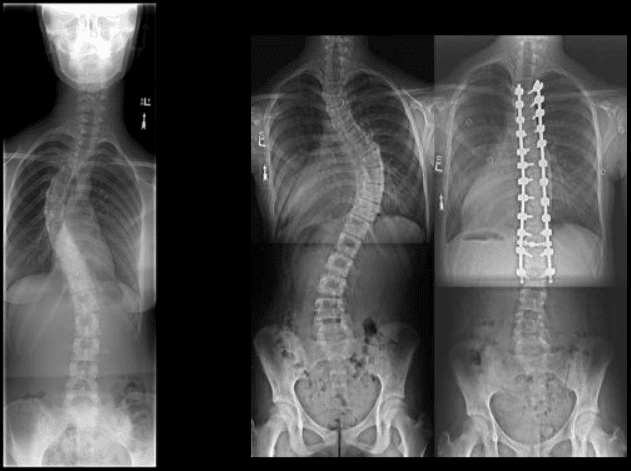

Studji dwar l-Immaġini

L-immaġini f'mard deġenerattiv tad-diska tintuża prinċipalment biex tiddeskrivi relazzjonijiet anatomiċi u karatteristiċi morfoloġiċi tad-diski affettwati, li għandha valur terapewtiku kbir fit-teħid ta 'deċiżjonijiet futuri għal għażliet ta' trattament. Kwalunkwe metodu ta 'immaġini, bħal radjografija sempliċi, CT, jew MRI, jista' jipprovdi informazzjoni utli. Madankollu, kawża sottostanti tista 'tinstab biss fi 15% tal-pazjenti billi l-ebda bidliet radjoloġiċi ċari ma huma viżibbli f'mard deġenerattiv tad-diska fin-nuqqas ta' ħernja tad-diska u defiċit newroloġiku. Barra minn hekk, m'hemm l-ebda korrelazzjoni bejn il-bidliet anatomiċi li dehru fuq l-immaġini u s-severità tas-sintomi, għalkemm hemm korrelazzjonijiet bejn in-numru ta 'osteofiti u s-severità ta' uġigħ fid-dahar. Bidliet deġenerattivi fir-radjografija jistgħu jidhru wkoll f'nies bla sintomi li jwasslu għal diffikultà biex jikkonformaw ir-rilevanza klinika u meta tibda l-kura. ("Marda tad-Diska Deġenerattiva" Fiżjopedja)

Trattament kirurġiku

It-trattament kirurġiku huwa riservat għal pazjenti bi terapija konservattiva falluta b'kont meħud tas-severità tal-marda, l-età, komorbidità oħra, kundizzjoni soċjo-ekonomika, u l-livell ta 'riżultat mistenni. Huwa stmat li madwar 5% tal-pazjenti b'mard deġenerattiv tad-diska jgħaddu minn operazzjoni, jew għall-marda tal-ġenbejn tagħhom jew għall-marda ċervikali. (Rydevik, Bjärn L.)

Proċeduri ta 'l-Ispina Lumbari

Il-kirurġija tal-ġenbejn hija indikata f'pazjenti b'uġigħ qawwi, b'tul ta '6 sa 12-il xahar ta' terapija tal-mediċina ineffettiva, li għandhom stenożi kritika tas-sinsla. Il-kirurġija ġeneralment hija proċedura elettiva ħlief fil-każ tas-sindrome ta 'cauda equina. Hemm żewġ tipi ta 'proċeduri li għandhom l-għan li jinvolvu fużjoni spinali jew dekompressjoni jew it-tnejn. ("Marda tad-Diska Deġenerattiva: Sfond, Anatomija, Patofiżjoloġija.")

Fużjoni spinali tinvolvi li twaqqaf movimenti fuq segment vertebrali bl-uġigħ sabiex tnaqqas l-uġigħ billi tgħaqqad diversi vertebri flimkien billi tuża tilqim tal-għadam. Huwa meqjus effettiv fuq medda twila ta 'żmien għal pazjenti b'mard deġenerattiv tad-diska li għandhom malalinament spinali jew moviment eċċessiv. Hemm bosta approċċi għall-kirurġija tal-fużjoni. (Gupta, Vijay Kumar, et al)